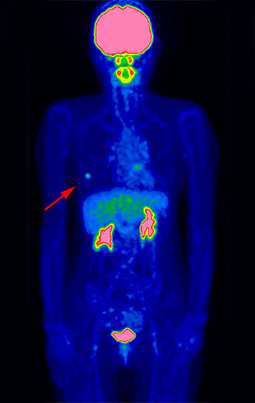

治療後経過観察にて以前の病変近傍に新たな病変出現(再発)

悪性リンパ腫